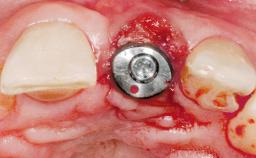

Late Placement of an Implant in a Maxillary Left Central Incisor Site

A 30-year-old female patient had lost tooth 21 and was referred to our clinic for consultation and treatment. Due to advanced apical infection, tooth 21 had been extracted two months earlier at another clinic and an acrylic-resin tooth had been bonded to the adjacent teeth. The patient desired implant treatment to avoid any damage to the adjacent natural teeth. While the patient had no history of any systemic disorder, she was a heavy smoker and exhibited medium to advanced periodontitis in the entire jaw. After the initial treatment to achieve a pocket probing depth of less than 4 mm and no bleeding on probing, a decrease in the height of the papillae mesial and distal to the extraction site and overall gingival recession were observed.

Type of Implants One-Piece|Reduced-Diameter

Bone Augmentation Horizontal|Staged